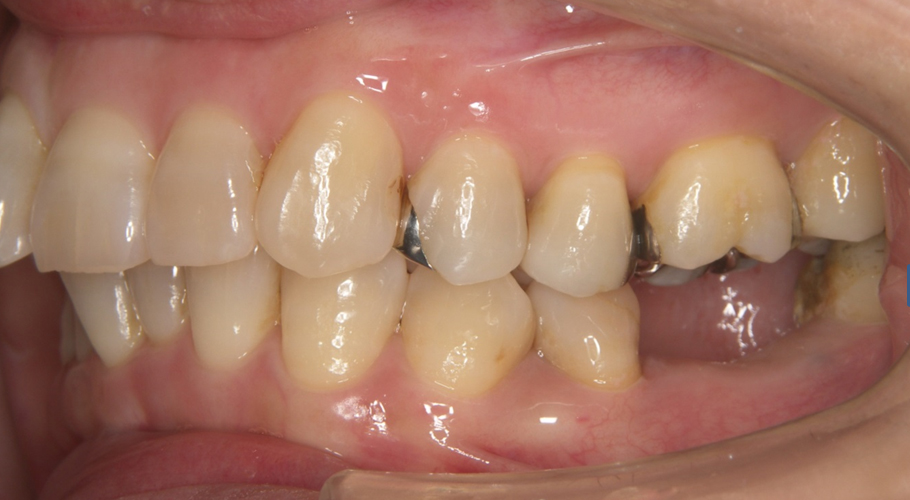

| 症状 | 奥歯のブリッジが取れてしまって食事がしにくい |

| 原因 | ブリッジ下の2次カリエス(虫歯の再発) 咬み合わせの不調和による咬合力の不均衡 |

| 治療法 | 矯正治療 自家歯牙移植 メタルボンドセラミッククラウン |

| 治療費(目安) | 自家歯牙移植 ¥54,000(料金改定前) メタルボンドセラミッククラウン 1歯¥10,8000(料金改定前) |